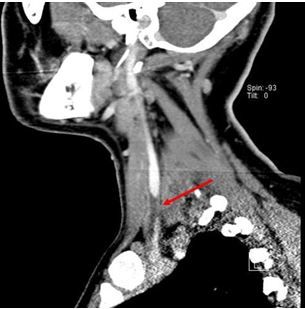

Fig 2. CT neck, sagital view shows thrombus in left internal jugular vein.

Later, a CT scan of the neck was performed. Results showed mild nonspecific thickening of the left tonsillar pillar and a thrombus in left internal jugular vein (Figures 2, 3, and 4, click to enlarge).